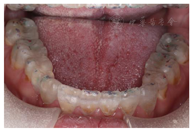

垫,口内戴入透明

垫后与

架上咬合一致,正中咬合时后牙功能尖多点接触,前牙轻接触,侧方运动时右侧尖牙引导,左侧23、24、25组牙引导。嘱患者发S音,评估前牙的位置及垂直距离,发F音和V音,评价切牙的长度和形状(图17,图18,图19,图20,图21,图22,图23)。